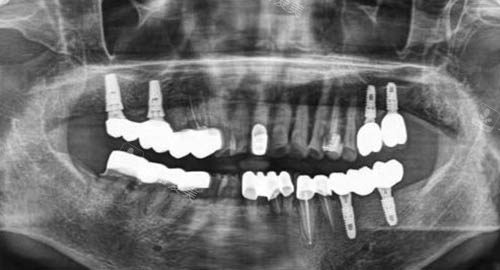

多颗牙齿种植ct

三、吉诚口腔在诊疗过程中如何维持患者的舒适体验?

吉诚口腔非常在意患者的诊疗体验。

在环境方面,医院的诊疗环境干净整洁、温馨舒适,让患者在就诊过程中感受到轻松和安心。

在服务方面,医护人员热情周到,会耐心地解答患者的疑问,缓解患者的紧张情绪。

在技术操作上,医生会尽量采用小创口技术,减少患者的痛苦。

例如,在种植牙和正畸治疗中,较高的技术和设备能够降低手术创伤,缩短修养时间,让患者在舒适的状态下完成治疗。